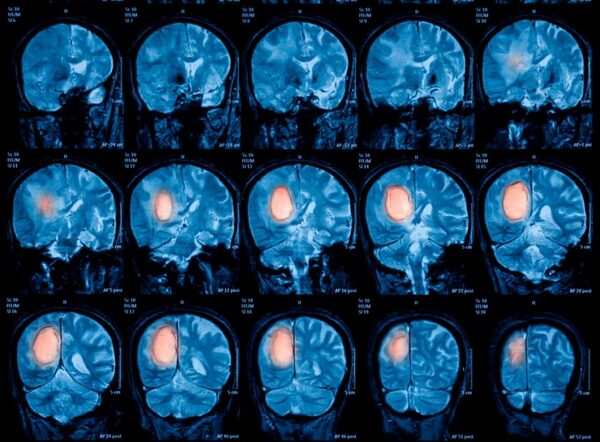

La Dra. Neurocirujana Gabriela Moguilner, explicó a la 1080 AM que este tipo de cirugías se realiza cuando aparecen gliomas (tumores primarios del sistema nervioso central que se ubican en el cerebro). Cuando los mismos afectan a las funciones como el habla o el movimiento, es cuando se precisa una intervención con el paciente despierto.